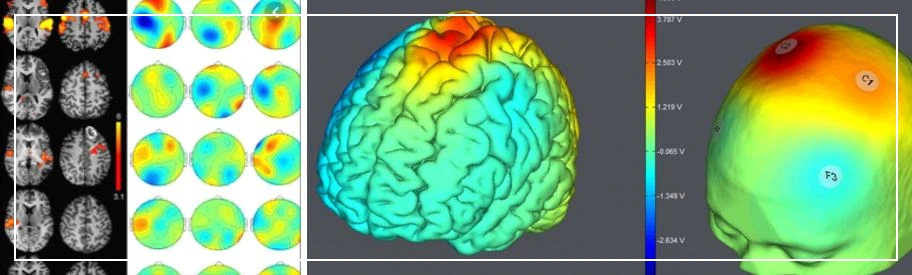

리더십과 뇌과학을 연계한 연구가 흥미로워 소개해 보고자 한다. 먼저 우리 뇌의 구조를 살펴볼 필요성이 있다. 독일 해부학자 Brodmann에 의하면 뇌는 1 ~ 52번 영역으로 구분할 수 있는데, 각각의 영역에서 발생하는 뇌파를 탐지하여 활성화되는 부위를 통해 각각의 기능을 알아낼 수 있다. 리더의 양심도 마찬가지다.

뇌의 기능을 분석하기 위해서는 fMRI(자기공명), qEEG(뇌파검사)를 활용한다. fMRI기법은 뇌의 특정 영역에서 변화하는 혈류량을 측정하기 위함이다. 반면, qEEG기법은 간질이나 정신질환 등 뇌파의 변화를 탐지하기 위한 측정의 목적으로 사용한다.

qEEG(뇌파)를 통해 뇌의 활성화 부위를 측정할 수 있다

뇌는 무수히 많은 신경망으로 연결되어 있는데, 휴식기에 있을 때에는 우측의 DMN(Default Mode Network) 네트워크 부위가 활성화되는 것으로 알려져 있다. 반면, 뇌가 일을 할 때에는 TPN(Task Positive Network) 네트워크 영역이 활성화 되게 된다.

뇌의 우측에 DMN, 좌측에 TPN이 위치한다

지금까지의 연구결과들에 의하면 DMN 영역이 윤리성을 포함하는 사회적 역량(social competency)에 관여하는 것이 흥미롭다. 특히, DMN 영역은 윤리적 리더십에 긍정적인 관계를 보이며 상대주의(relativism)에는 부정적 영향을 나타낸다(Waldman et al., 2017). 사회적 역량은 나와 타인 간의 상호작용을 통해 정체감을 확립하여 다른 사람과 사회적 관계를 맺고 유능한 사회 구성원으로 살아가는 데 필요한 역량인데, 사회의 구성원으로서 요구되는 책임감을 포함하기 때문에 윤리성과 높은 상관성이 있다.

연구 방법도 매우 흥미로운데, 우선 리더들에게 윤리적 딜레마 상황을 시나리오로 제공하고 fMRI, qEEG를 통해 뇌의 활성화 부위를 측정한다. 동시에 설문을 통해 리더의 윤리성에 대해 함께 일하는 동료, 구성원들에게 응답을 받아 분석에 사용한다.

윤리성이 높은 리더의 뇌를 MRI로 찍어보면 DMN부위가 활성화된다